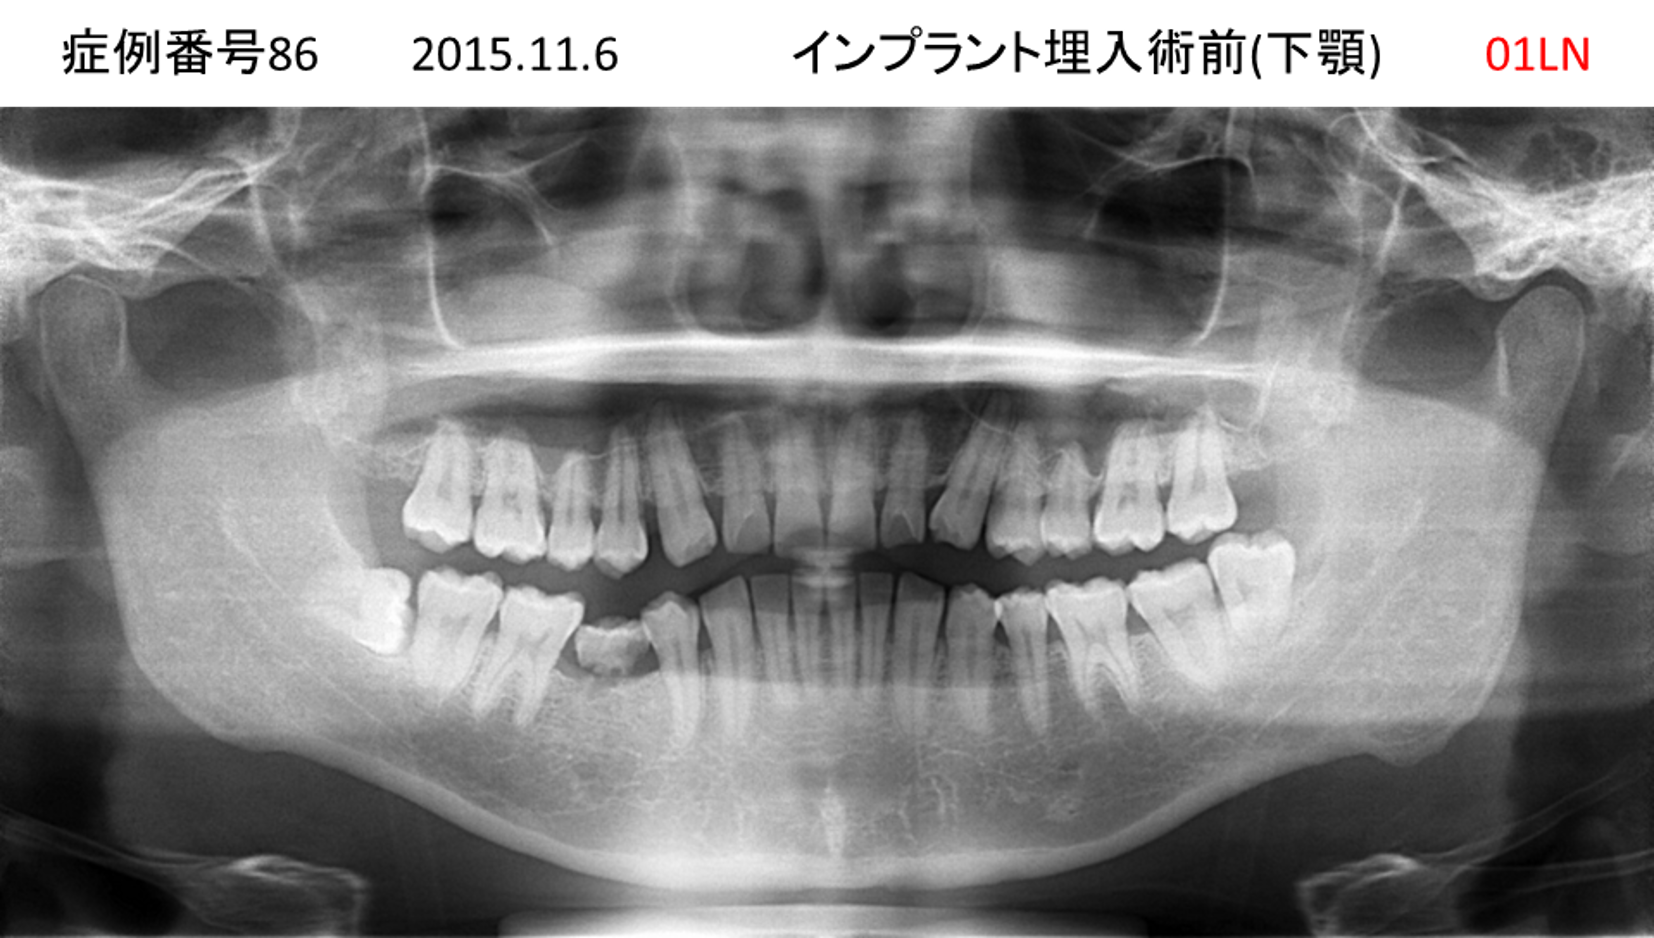

ご飯を美味しく食べたい/人前で笑えるようになりたい患者様のインプラント症例

| 治療名称 |

インプラント |

| 治療費用 |

480万円+税 |

| 治療期間 |

6か月 |

| 患者さんの症状(主訴) |

おいしいご飯が食べられるようになりたい 人前で笑えるようになりたい |

| 治療内容 |

サイナスリフト 抜歯即時インプラント |

| 治療結果 |

何でも食べられるようになった 人前で大口を開けて笑えるようになった |

| 治療の注意点(リスク/副作用) |

インプラントが壊れた場合は再治療が必要 |